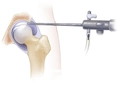

Düşme Sonucu Kalça Kırığı Riski Nasıl Azaltılır?Düşme, özellikle yaşlı bireylerde kalça kırıkları gibi ciddi yaralanmalara yol açabilen önemli bir sağlık sorunudur. Bu makalede, düşme sonucu kalça kırığı riskini azaltma yöntemleri üzerinde durulacaktır. Düşme Nedenleri ve Risk FaktörleriDüşme olayları, çeşitli faktörlerin birleşimi sonucunda gerçekleşir. Bu faktörler arasında;

SonuçDüşme sonucu kalça kırığı riski, yaşlı bireylerde önemli bir sağlık sorunu oluşturmaktadır. Ancak, yukarıda belirtilen önlemler ve stratejilerle bu risk önemli ölçüde azaltılabilir. Denge ve kuvvet artırıcı egzersizler, düzenli sağlık kontrolleri, çevresel düzenlemeler ve sağlıklı beslenme alışkanlıkları, bireylerin bu riski minimize etmelerine yardımcı olacaktır. Toplum genelinde bilinçlendirme çalışmaları da bu konuda kritik bir öneme sahiptir. |